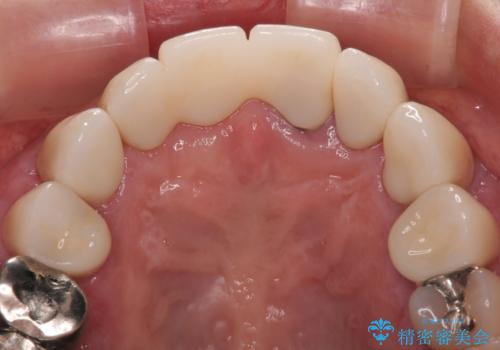

前歯のインプラントは埋入されたポジションが望ましい位置ではなく、インプラントを活用して段差を回収することは不可能と判断し、歯肉移植によりインプラントを隠して、ブリッジにて歯肉ラインを整えることとしました。

臼歯部の治療も必要と判断されましたが、前歯部を中心とした審美領域をオールセラミッククラウンによる補綴治療を行うこととしました。

帰国時のみの治療であったため、治療期間は長くなりましたが、最小限の来院回数で、気になっていた前歯をきれいに整えることができました。